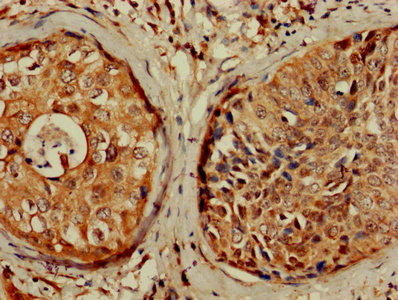

IHC image of CSB-PA005086DA01HU diluted at 1:1200 and staining in paraffin-embedded human testis tissue performed on a Leica BondTM system. After dewaxing and hydration, antigen retrieval was mediated by high pressure in a citrate buffer (pH 6.0). Section was blocked with 10% normal goat serum 30min at RT. Then primary antibody (1% BSA) was incubated at 4°C overnight. The primary is detected by a biotinylated secondary antibody and visualized using an HRP conjugated SP system.